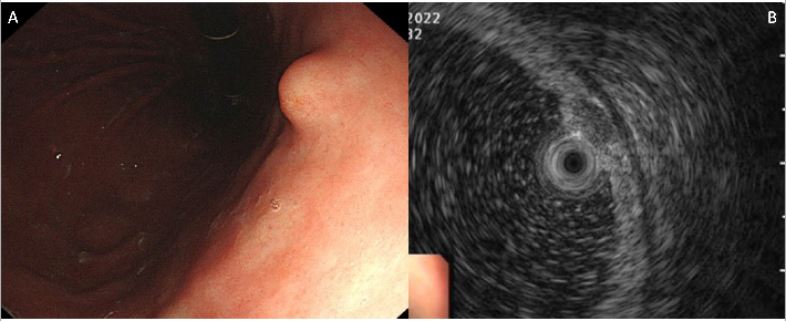

Endoscopy serves as a cornerstone in the initial assessment of patients suspected of harboring gastric NETs, facilitating visual inspection of the tumor and acquisition of biopsy specimens for subsequent histological evaluation [1]. Type III tumors tend to emerge as solitary, larger lesions, distinguishing them from the multifocal distribution and smaller size characteristic of type I and II gastric NETs. Moreover, type III gastric NETs may appear as hard, yellow and hypoechoic subepithelial lesions (Figure 1), ulcerated masses, or polypoid lesions on endoscopic examination [15]. Their features frequently mimic other gastric neoplasms like adenocarcinomas or gastrointestinal stromal tumors [14].

In addition to standard esophagogastroduodenoscopy, Endoscopic Ultrasound (EUS) may be employed for a more detailed assessment of tumor depth [1,8] (Figure 1), although there is currently no universally defined size threshold prompting this procedure. Typically, lesions smaller than 8-10 mm may not be suitable for fine needle biopsy during EUS, and those smaller than 5 mm might pose challenges for endosonographic visualization. EUS offers the potential advantages of identifying muscularis propria invasion, which could preclude complete endoscopic resection, as well as assessing lymphadenopathy. While EUS is recommended for type I and II disease as dictated by clinical need, the ENETS suggests EUS for type III disease to assess lymphadenopathy and tumor depth. If deemed resectable, the preferred approach is either endoscopic or surgical resection, though international guidelines lean toward endoscopic resection, particularly for superficial lesions measuring less than one centimeter with “low-grade” histology [1,8].

Figure 1: Gastric neuroendocrine tumor type III. (A) A subepithelial tumor located in the gastric lower body as observed during endoscopy. (B) A homogeneous hypoechoic mass measuring 0.4 cm x 0.6 cm, demonstrating invasion into the submucosal layer as evidenced by endoscopic ultrasound.